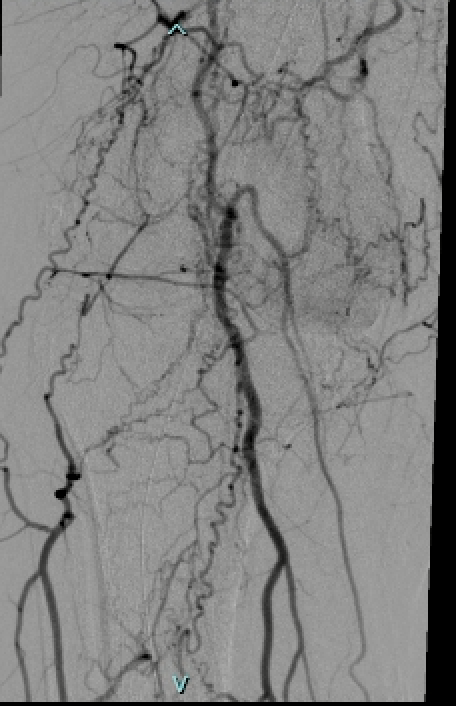

.@LucasRCmd, MPH; @HiroSparks, MD; Kara E. Masterson, MSN, NP; Scott J. Genshaft, MD; @AdamPlotnik, MD; and Siddharth A. Padia, MD, contributed to this open access article. See what they've been working on! brnw.ch/21wPx6v